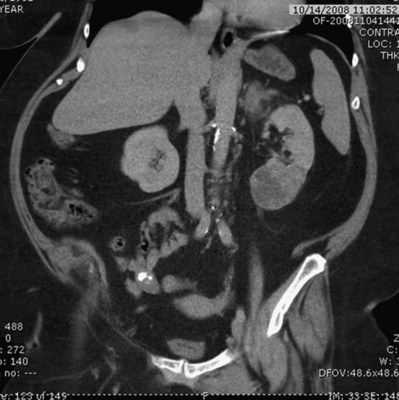

Before partial nephrectomy, evaluation of patients with renal cortical tumors should include imaging to identify locally extensive or metastatic disease. Preoperative imaging should also delineate relevant regional anatomy, intrarenal anatomy, and vasculature to minimize blood loss and damage to adjacent renal parenchyma. Invasive renal arteriography has largely been replaced by noninvasive 3D CT angiography, which offers excellent anatomic detail. 3D CT integrates information from arteriography, venography, excretory urography, and conventional two-dimensional CT into a single imaging modality (Fig. 54–130). In addition to tumor staging, 3D reconstructions of contrast-enhanced CT angiograms, MR images, or MR venograms are useful for planning site and extent of planned resection and to determine proximity to the renal hilum, intrarenal vasculature, and collecting system (Fig. 54–131). 3D CT accurately demonstrates involvement of the collecting system by tumor (Derweesh et al, 2003).

Figure 54–131 A, Contrast-enhanced CT scan demonstrating right renal mass. B, Three-dimensional reconstruction demonstrates a large intrarenal component to the mass. C, Arterial reconstruction shows lower pole renal artery in close proximity to the renal mass.